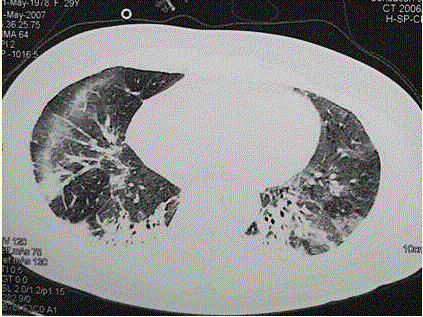

问题  患者女,29岁。间断干咳10年余,加重4个月,伴进行性呼吸困难1个月。病程中出现双手及双足非凹陷性肿胀、双侧膝关节及双侧肘关节对称性肿痛,面部出现细小红色丘疹。体检:T 36.5℃,P 88次/min,R 22次/min,BP 110/75 mmHg,SpO 93%(自然)。额部、前胸及后背散在红色小丘疹,双肺呼吸音增强,双肺中下肺野可闻及爆裂音,右肺明显。胸部CT 如图所示。 为明确诊断应检查的项目包括

选项 A、痰培养+药敏 B、肺功能检查,包括通气及弥散功能检查 C、军团菌尿抗原测定 D、血常规 E、支气管镜检查 F、痰涂片抗酸染色 G、肺癌筛查 H、经皮肺活检

答案 ABCDEH